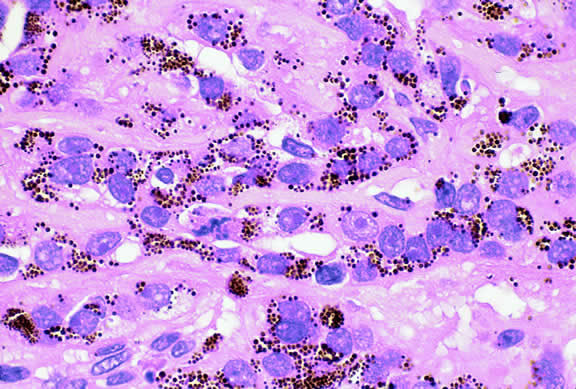

Choroidal melanomas produce abnormalities in the overlying retinal pigment epithelium including atrophy, hyperplasia, and the formation of drusen and drusenoid material.92 The overlying retina often shows photoreceptor loss and may develop cystoid edema. The latter tends to be more common in slower growing lesions, especially choroidal hemangiomas. After Bruch's membrane has ruptured, the vessels located in the mushrooming head of the tumor are often quite prominent, reflecting vascular stagnation caused by the compression at the waist of the tumor (see Fig. 22). Aggregates of macrophages that have ingested periodic acid-Schiff (PAS)-positive lipofuscin pigment and melanin from the damaged retinal pigment epithelium can be found in the subretinal fluid (Figs. 39 to 41). These are evident ophthalmoscopically as clumps of orange pigment that serve as a clinical marker for an actively growing neoplasm.80,81

Fig. 39. Juxtapapillary melanoma with orange pigment. Orange pigment is a clinical marker for an actively growing tumor.

Fig. 41. Orange pigment. Orange pigment is comprised of aggregates of macrophages that have phagocytized periodic acid-Schiff (PAS)-positive lipofuscin and melanin pigment released by retinal pigment epithelial cells that have been disrupted by the actively growing tumor. (Periodic acid-Schiff, × 100.)